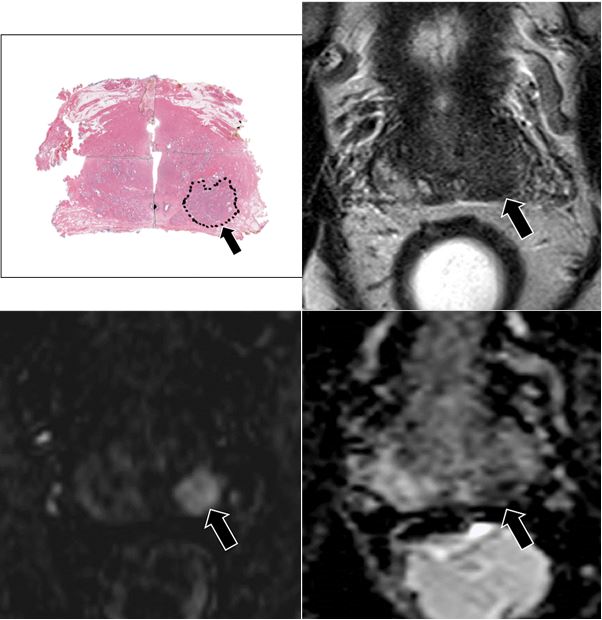

Defining which prostate cancers are potentially aggressive and provide early metastases is essential for patient management. It seems that visibility with MRI is a prognostic predictor.

Article: Correlation between MRI phenotypes and a genomic classifier of prostate cancer: preliminary findings